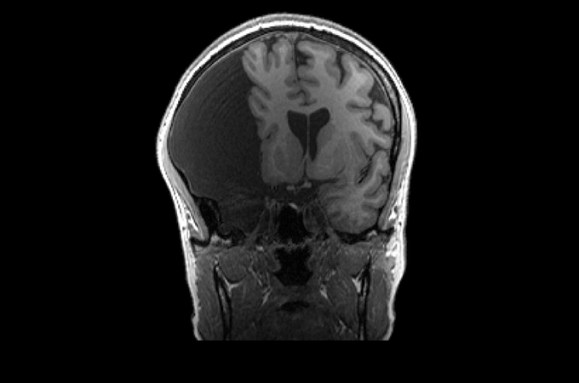

Elyse G. found out she lacked most of her left temporal lobe when she was 25 years old. The brain region is typically crucial for speech and language — but until her brain was scanned (three views shown), no one knew Elyse was missing hers.

Looking at her brain scans is a different story. It’s as if someone has knocked over a bottle of ink. The darkness pools inside her skull near her left ear, a puddle of fuliginous black. Inside the splotch, there’s no white matter or gray matter, no blood vessels or tissue at all.

Elyse says you don’t have to be a neurosurgeon to spot what’s different about her brain: “There’s a big honking piece missing!”